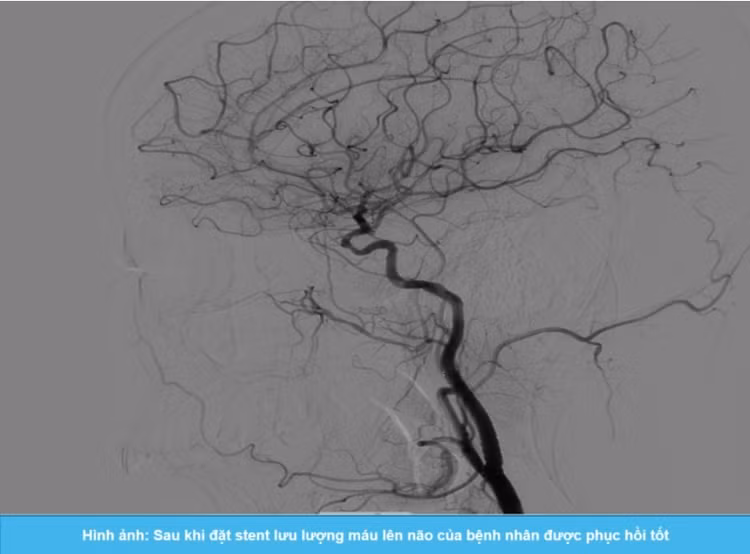

Dưới sự hỗ trợ của hệ thống chụp mạch số hóa xóa nền DSA, ThS.BS Giáp Hùng Mạnh cùng ê-kíp can thiệp đã tiến hành nong động mạch cảnh trong bên trái bị hẹp và đặt stent thành công, giúp mở rộng lòng mạch hiệu quả, phục hồi lưu lượng máu lên não cho bệnh nhân.

Sau can thiệp, bệnh nhân phục hồi tốt, các triệu chứng thần kinh cải thiện rõ rệt, tỉnh táo, không có biến chứng sau thủ thuật.